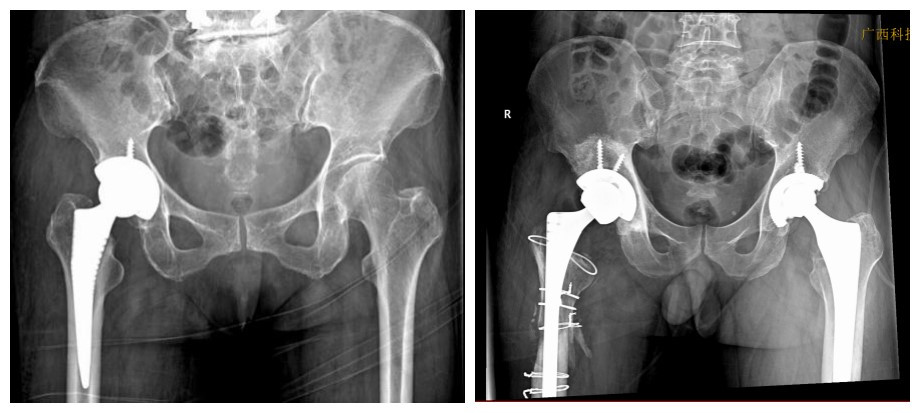

1、髋关节:股骨头缺血性坏死、髋关节发育不良、髋关节撞击综合征、臀肌挛缩、髋关节术后假体松动

(1)人工关节置换及翻修术:熟练开展人工髋、膝关节置换及翻修、膝关节单髁置换、踝关节表面置换,特别是微创全髋关节置换术(DAA),显著缩短患者住院时间,提高术后生活质量。